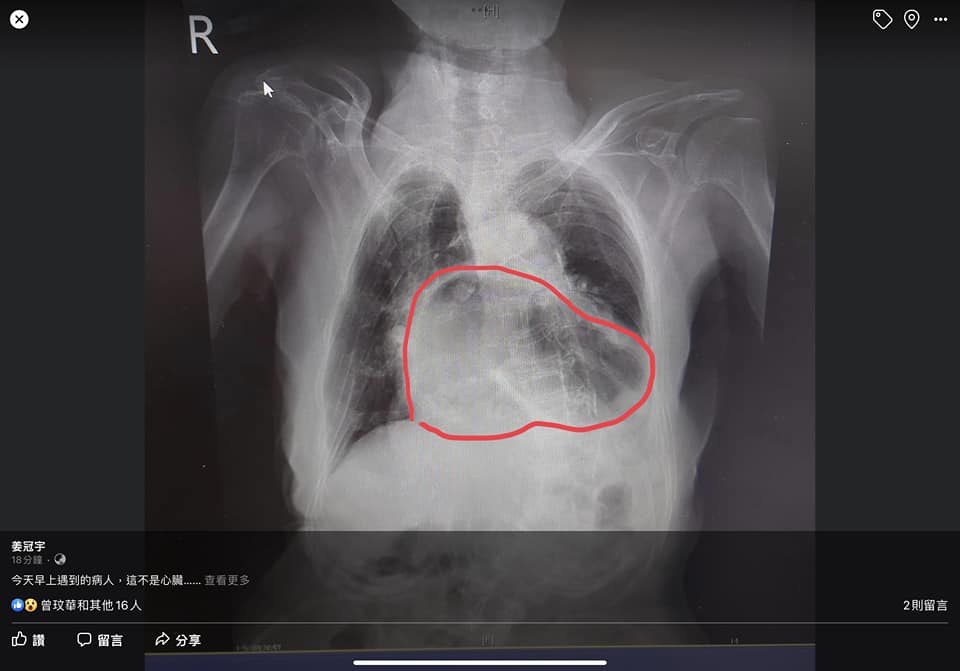

「這不是心臟,而是胃!」姜冠宇醫師2日在臉書分享病例,一名阿嬤有咳嗽的老毛病,還有呼吸不順等症狀,結果一照X光竟發現阿嬤把胃都咳翻了,他解釋這是經典的「咳到胃翻出來」,只能動手術改善,縫補橫膈膜,但偏偏阿嬤不願意動刀,唯一辦法就是少量進食。

姜冠宇醫師進一步說明,該症狀就是「胃疝脫」,錯位突破橫膈膜擠入胸腔,這不能只有專注在消化道的問題,因為不可能一、兩次嗆到就咳成這樣,「這明顯是很長期的咳嗽問題」,至於背後有沒有其他慢性呼吸道疾病,像是COPD或氣喘,甚至是潛在感染後的後遺症,仍需後續評估並給予治療,否則沒得改善還會變得更加嚴重。

姜冠宇醫師擔心大家看不懂X光,還特別用紅筆標示出來:「原本是心臟的位置,變成了胃」,而且還扭曲反折,如果不提早治療改善,日後還會有更嚴重的胃食道逆流,這是因為胃的位置不對,導致吞食的食物是以非正常的狀態下抵達胃部,隨著酸液湧出,胸悶感及灼燒感也會更嚴重。